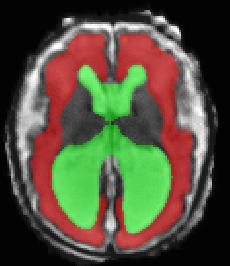

Limiting failures of machine learning systems is of paramount importance for safety-critical applications. In order to improve the robustness of machine learning systems, Distributionally Robust Optimization (DRO) has been proposed as a generalization of Empirical Risk Minimization (ERM). However, its use in deep learning has been severely restricted due to the relative inefficiency of the optimizers available for DRO in comparison to the wide-spread variants of Stochastic Gradient Descent (SGD) optimizers for ERM. We propose SGD with hardness weighted sampling, a principled and efficient optimization method for DRO in machine learning that is particularly suited in the context of deep learning. Similar to a hard example mining strategy in practice, the proposed algorithm is straightforward to implement and computationally as efficient as SGD-based optimizers used for deep learning, requiring minimal overhead computation. In contrast to typical ad hoc hard mining approaches, we prove the convergence of our DRO algorithm for over-parameterized deep learning networks with ReLU activation and a finite number of layers and parameters. Our experiments on fetal brain 3D MRI segmentation and brain tumor segmentation in MRI demonstrate the feasibility and the usefulness of our approach. Using our hardness weighted sampling for training a state-of-the-art deep learning pipeline leads to improved robustness to anatomical variabilities in automatic fetal brain 3D MRI segmentation using deep learning and to improved robustness to the image protocol variations in brain tumor segmentation. Our code is available at https://github.com/LucasFidon/HardnessWeightedSampler.